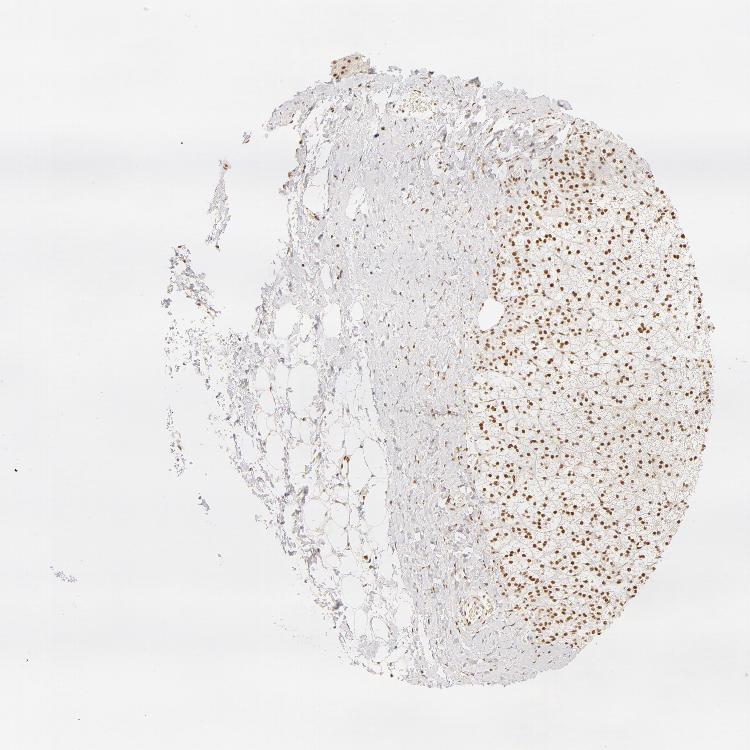

ADRENAL GLAND - Antibody stainingi

Antibody staining in the annotated cell types in the current human tissue is reported as not detected, low, medium, or high, based on conventional immunohistochemistry profiling in selected tissues. This score is based on the combination of the staining intensity and fraction of stained cells.

Each image is clickable and will lead to virtual microscopy that enables deeper exploration of all samples and also displays staining intensity scores, fraction scores and subcellular localization as well as patient and tissue information for each sample.

Antibody HPA001591

Glandular cells Medium